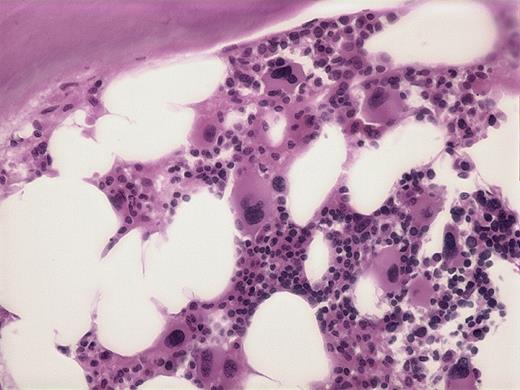

Trephine bone marrow biopsy has a characteristic appearance with increased numbers of megakaryocytes with hypolobulated nuclei. The number of blasts in the bone marrow is below 5%. A hematoxylin and eosin stain was used here.